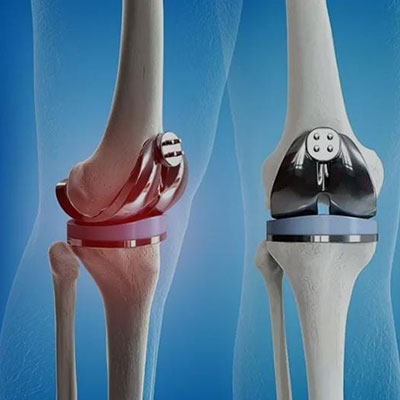

Knee replacement surgery involves removing damaged portions of the knee joint and replacing them with artificial components made of metal, ceramic or plastic. The procedure is usually recommended for individuals with severe arthritis, injury or other conditions that limit their ability to perform daily activities.

Knee replacement surgery typically lasts one to two hours and is performed under general or regional anesthesia. The surgeon makes an incision above the knee to access the joint, removes the damaged portions and implants the prosthetic components. The incision is then closed and the knee is bandaged.